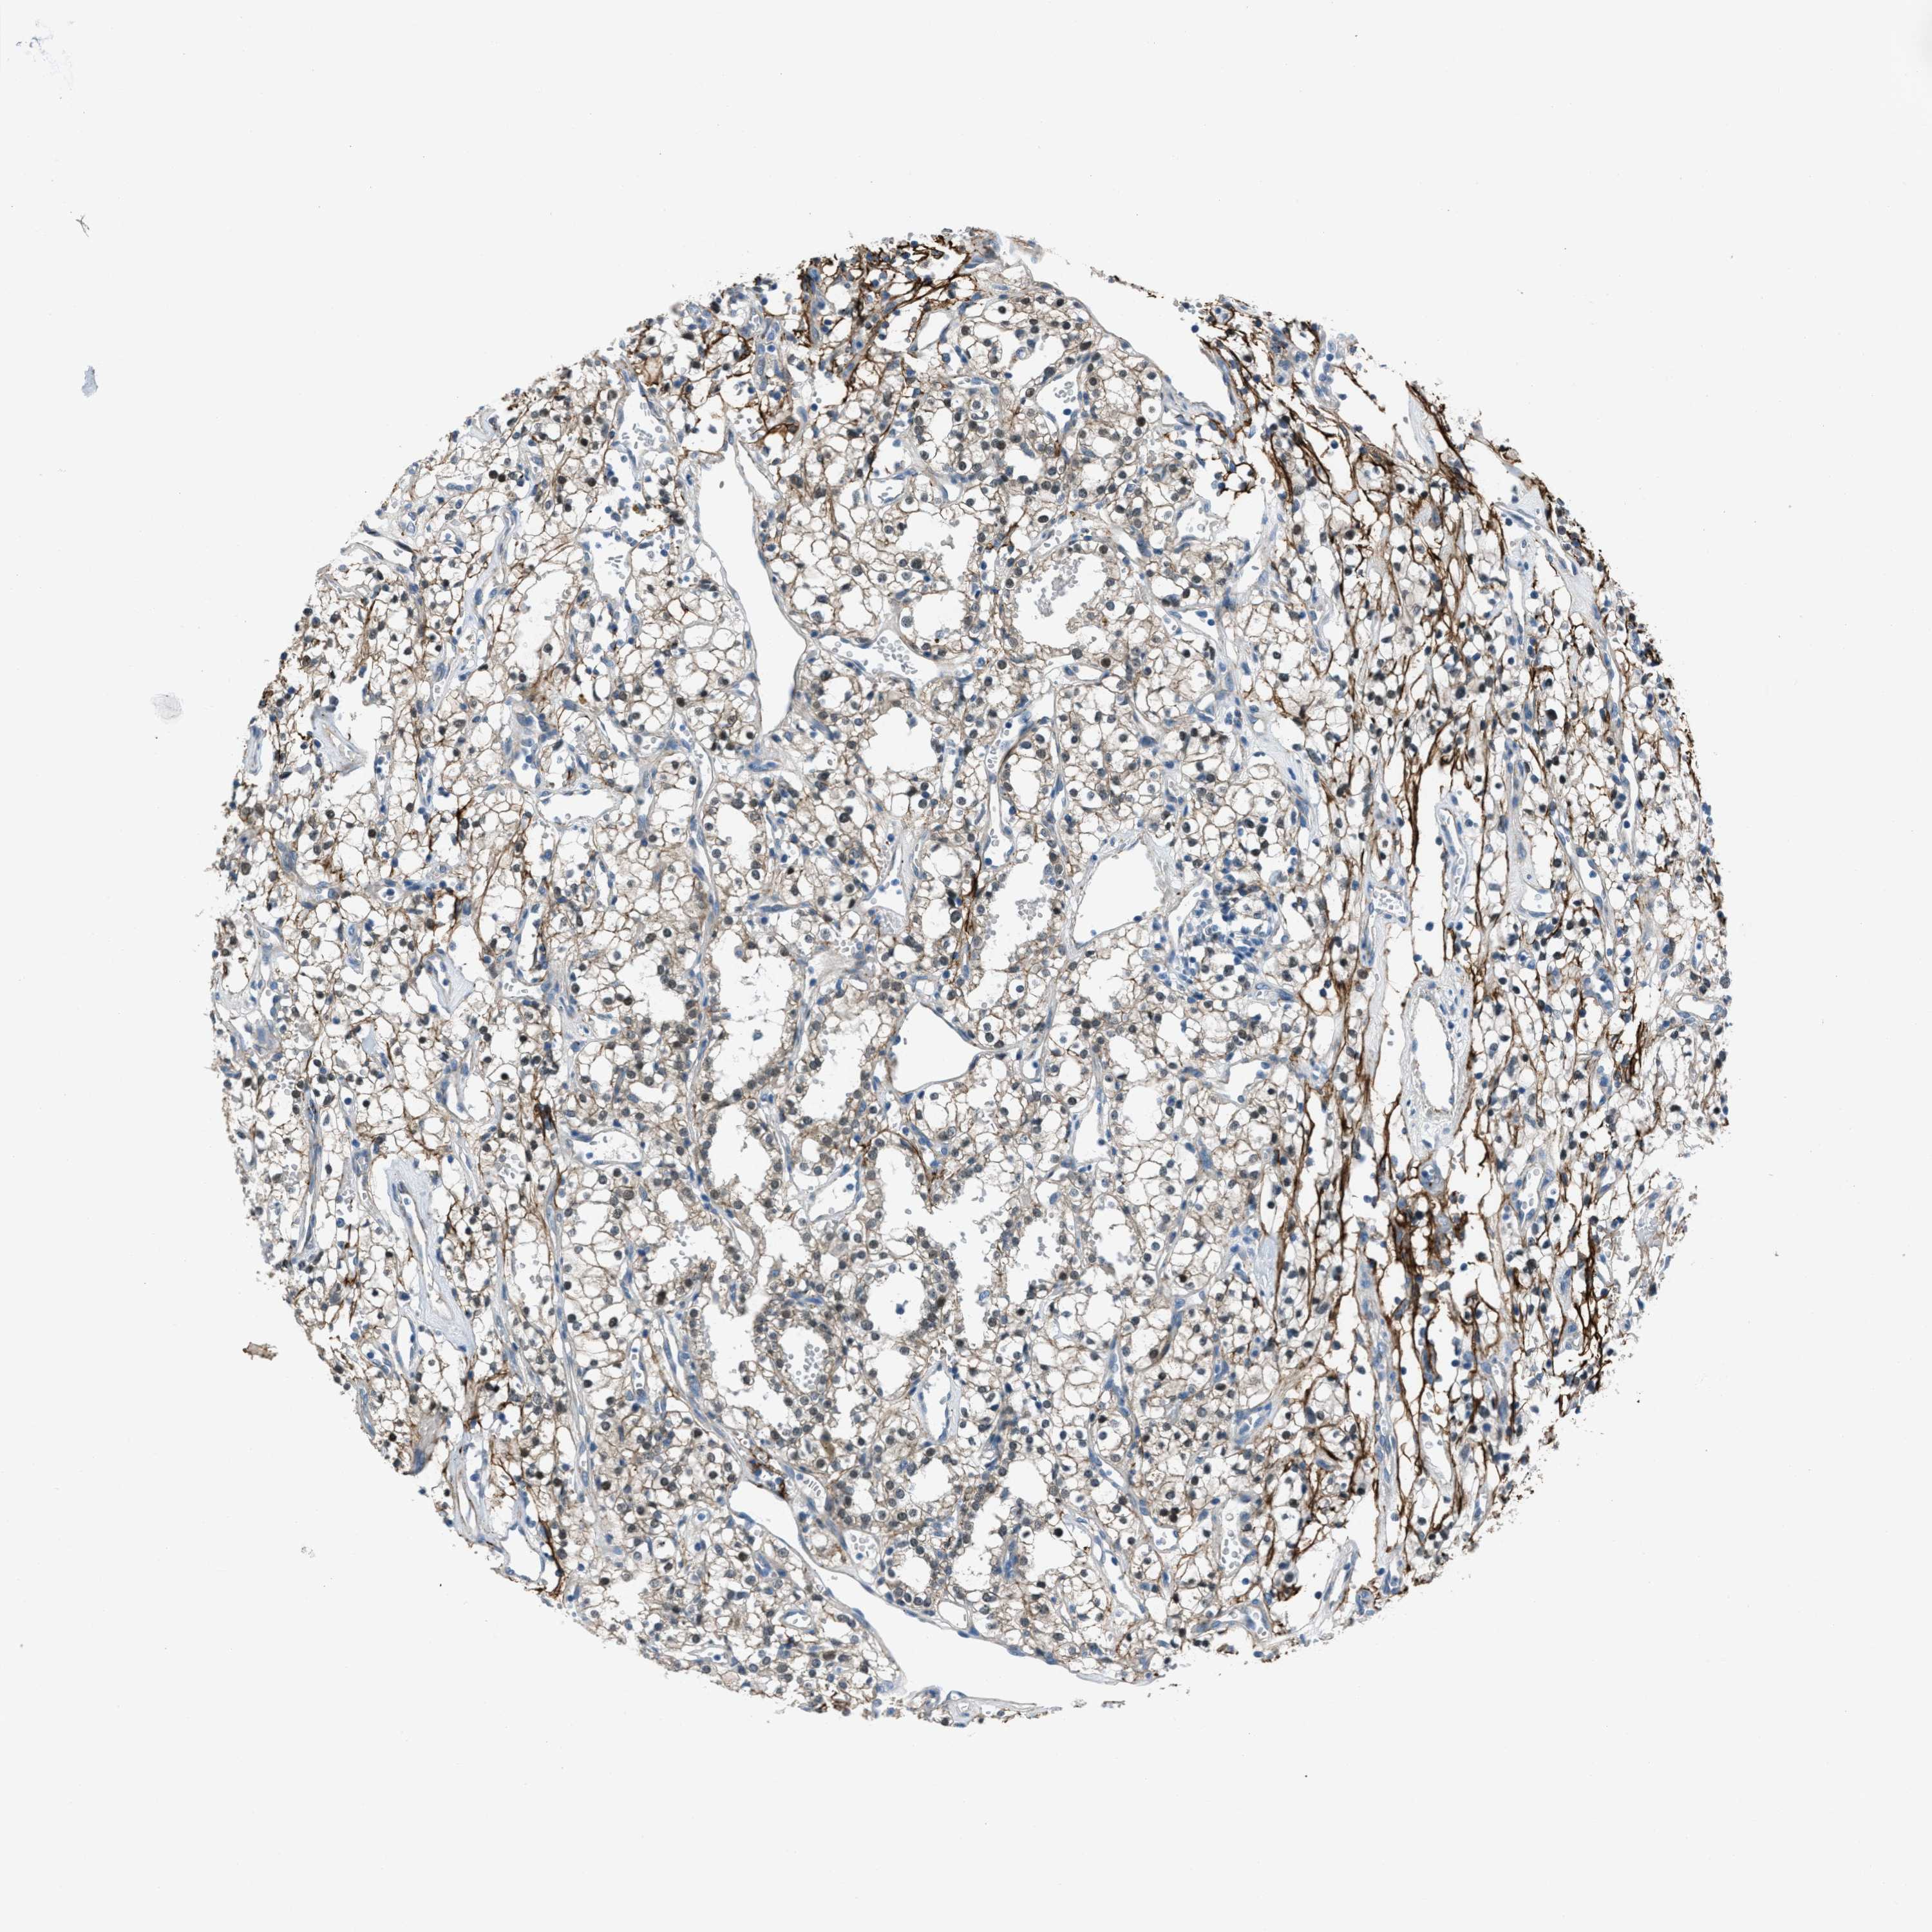

FBN1 is not prognostic in Kidney Renal Clear Cell Carcinoma (validation)

Best expression cut offi

When clicking on this number, the vertical dashed line indicating cut-off, the interactive survival plot, and the Kaplan-Meier curve will be adjusted to show results based on the best expression cut-off.

: 6.16

TCGA RNA samplesi

RNA-seq data is reported as average FPKM (number Fragments Per Kilobase of exon per Million reads), generated by the The Cancer Genome Atlas (TCGA) .

Normal distribution across the dataset is visualized with box plots, shown as median and 25th and 75th percentiles. Points are displayed as outliers if they are above or below 1.5 times the interquartile range. FPKM values of the individual samples are presented next to the box plot.

Average pTPM 7.1

Number of samples 100